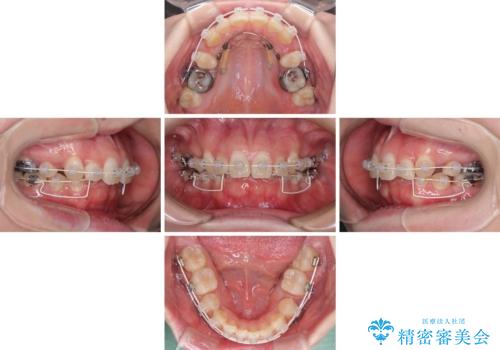

著しい八重歯を短期間で改善 ワイヤー装置による抜歯矯正

- 審美装置

下顎小臼歯の欠損により過蓋咬合となっていたため、下顎は臼歯を起こすことで咬み合わせを改善し、八重歯は第一小臼歯2本を抜歯し、補助装置を使用して速やかに改善することとしました。

著しい過蓋咬合の改善が必要であった割には、治療期間は2年強と標準的でした。

八重歯は3,4か月で速やかに改善されました。